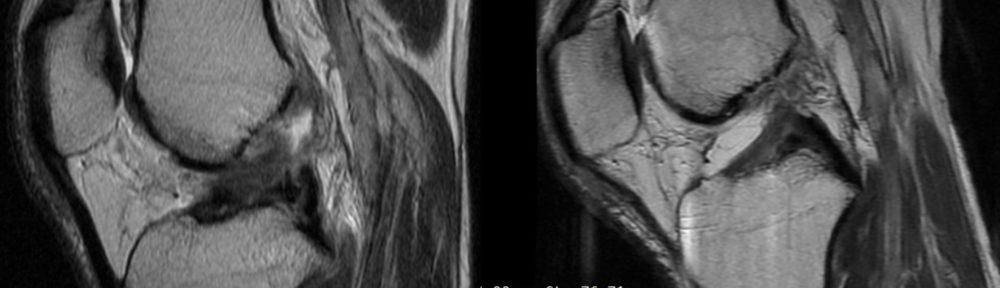

Valutazione iniziale(RM #1)

- Data: 7 aprile 2023

- Diagnosi: rottura completa del LCA del ginocchio destro

- Lettura indipendente (3 radiologi): concorde classificazione di Ihara IV(monconi indistinti / morfologia scadente)

Seconda RM(~4 mesi)

- Data: 31 agosto 2023

- Lettura indipendente (3 radiologi): concorde ACLOAS grado 2(assottigliamento/allungamento con continuità preservata)

- Interpretazione: dal quadro complesso Ihara IV a reperti indicativi di continuità ripristinata

- RM #1(07/04/2023): Ihara IV(concorde, 3/3 lettori)

- RM #2(31/08/2023): ACLOAS 2 — continuità ripristinata